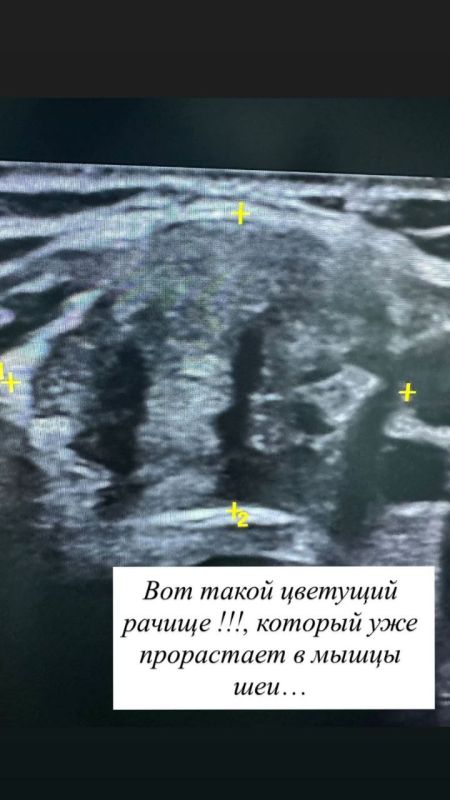

УЗИ ещё 3 года назад показало у девушки узел в щитовидке, который мог перерасти в рак. Вместо врача она доверилась шарлатанам, потому что «врачам лишь бы порезать кого-то».Итог: через 3 года мама девушки силой притащила её к врачу....